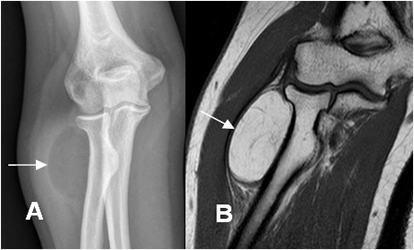

Fig 157 A. Lipoma.

A: Rx AP y B. RM coronal en STIR. Prominencia de tos tejidos blandos hacia la parte lateral del antebrazo, con imagen ovalada y con densidad de grasa, similar al tejido celular subcutáneo, que corresponde a lipoma.